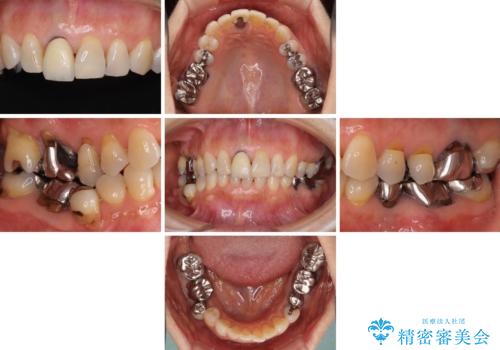

金属を全てセラミックに メタルフリー治療

- 口腔内にある銀歯を全て外したいとのことで来院された患者様です。

土台に含まれている金属も含め、口腔内の金属は全て除去し、抜歯しなければならない歯は抜歯し、オールセラミッククラウンやセラミックインレーにて治療することとしました。

上下奥歯の抜歯を同時期に行わず、下顎の治療を終えてから上顎を抜歯して治療を進めたため、1年ほどの期間を要しました。

口の中を一切気にしなくて良くなり、患者様には大変満足していただきました。